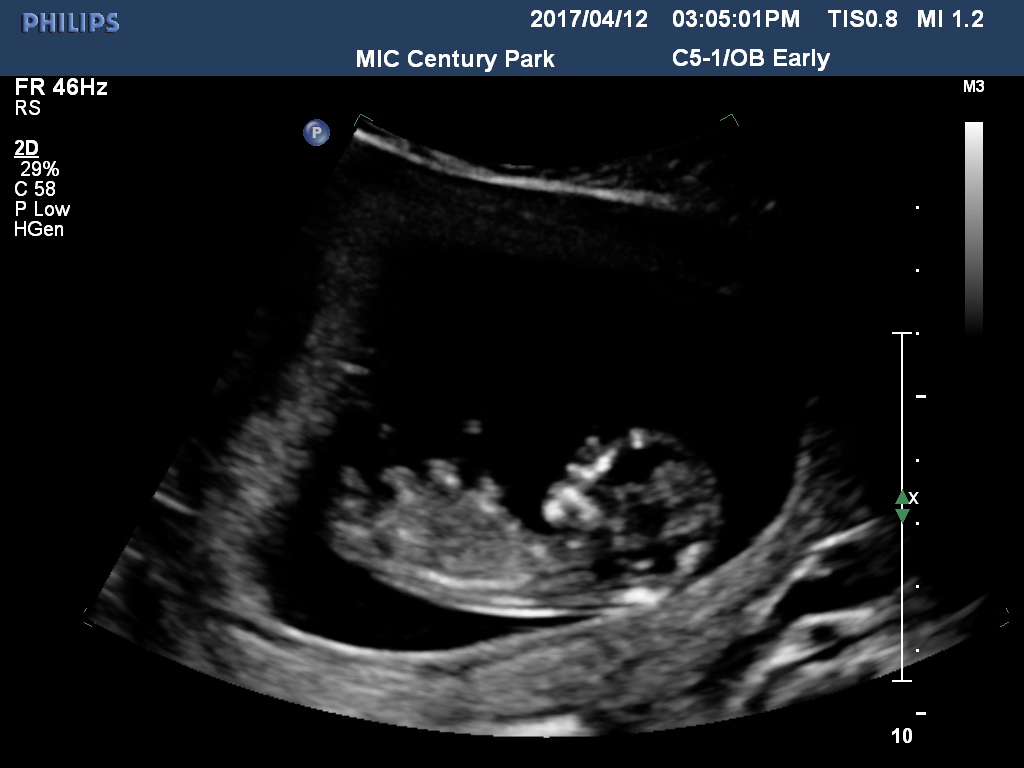

Any ideas if it's a girl or boy nub? I don't even see the nub at all...?